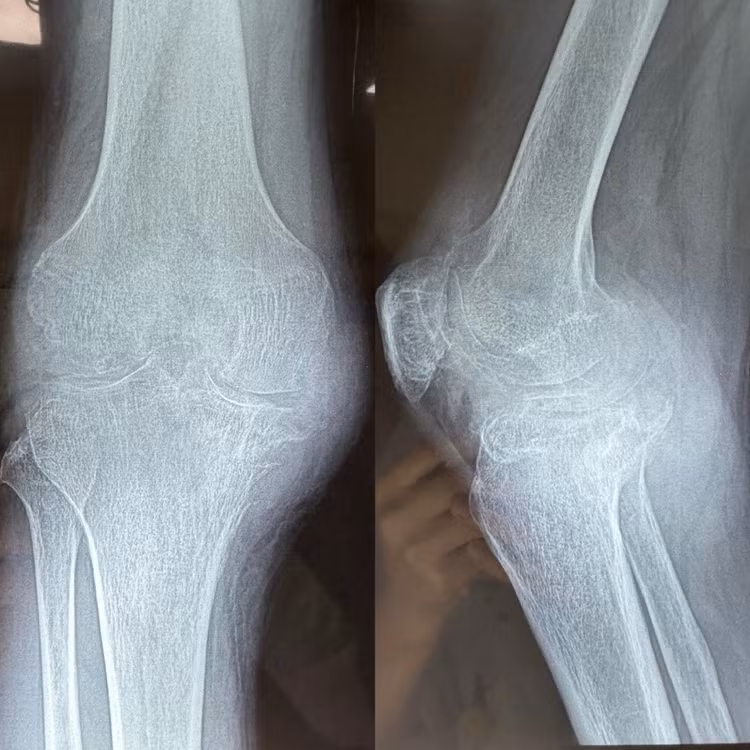

Trước phẫu thuật, khớp gối bên phải của anh T co cứng ở tư thế gấp, mất hoàn toàn vận động, khớp gối bên trái cũng hạn chế nhiều.

| Các hạt tophi phát triển ngày càng lớn phá hủy hết khớp bệnh nhân |